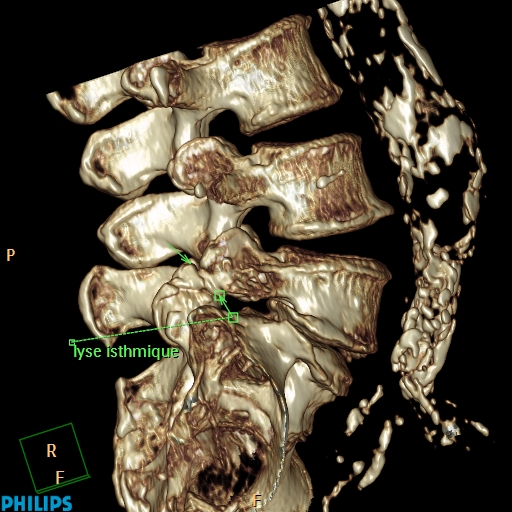

Spondylolyse et spondylolisthésis isthmique sont des aspects différents d’une affection dont la variabilité clinique est remarquable. Quantification du glissement. Clinique. Spondylolyse isthmique. Clinique. Imagerie. Formes cliniques. Indications thérapeutiques. Techniques chirurgicales.. La lyse se située plus souvent à l’étage L5/S1 mais peut parfois se retrouver à l’étage L4/L5. il est habituel que classer le glissement, occasionné par la lyse, en 4 stades de Meyerding. TRAITEMENT. Avant tout il est médical avec des antalgiques, de la rééducation associée au besoin à des infiltrations.

spondylolisthesis par lyse isthmique bilaterale spondylolisthesis traitement espace francilien

spondylolisthesis par lyse isthmique bilaterale spondylolisthesis traitement espace francilien

Lyse isthmique INTERVENTIONAL RADIOLOGY

La lyse isthmique et le spondylolisthésis chez l’enfant

LE SPONDYLOLISTHESIS PAR LYSE ISTHMIQUE BASES ANATOMIQUES YouTube